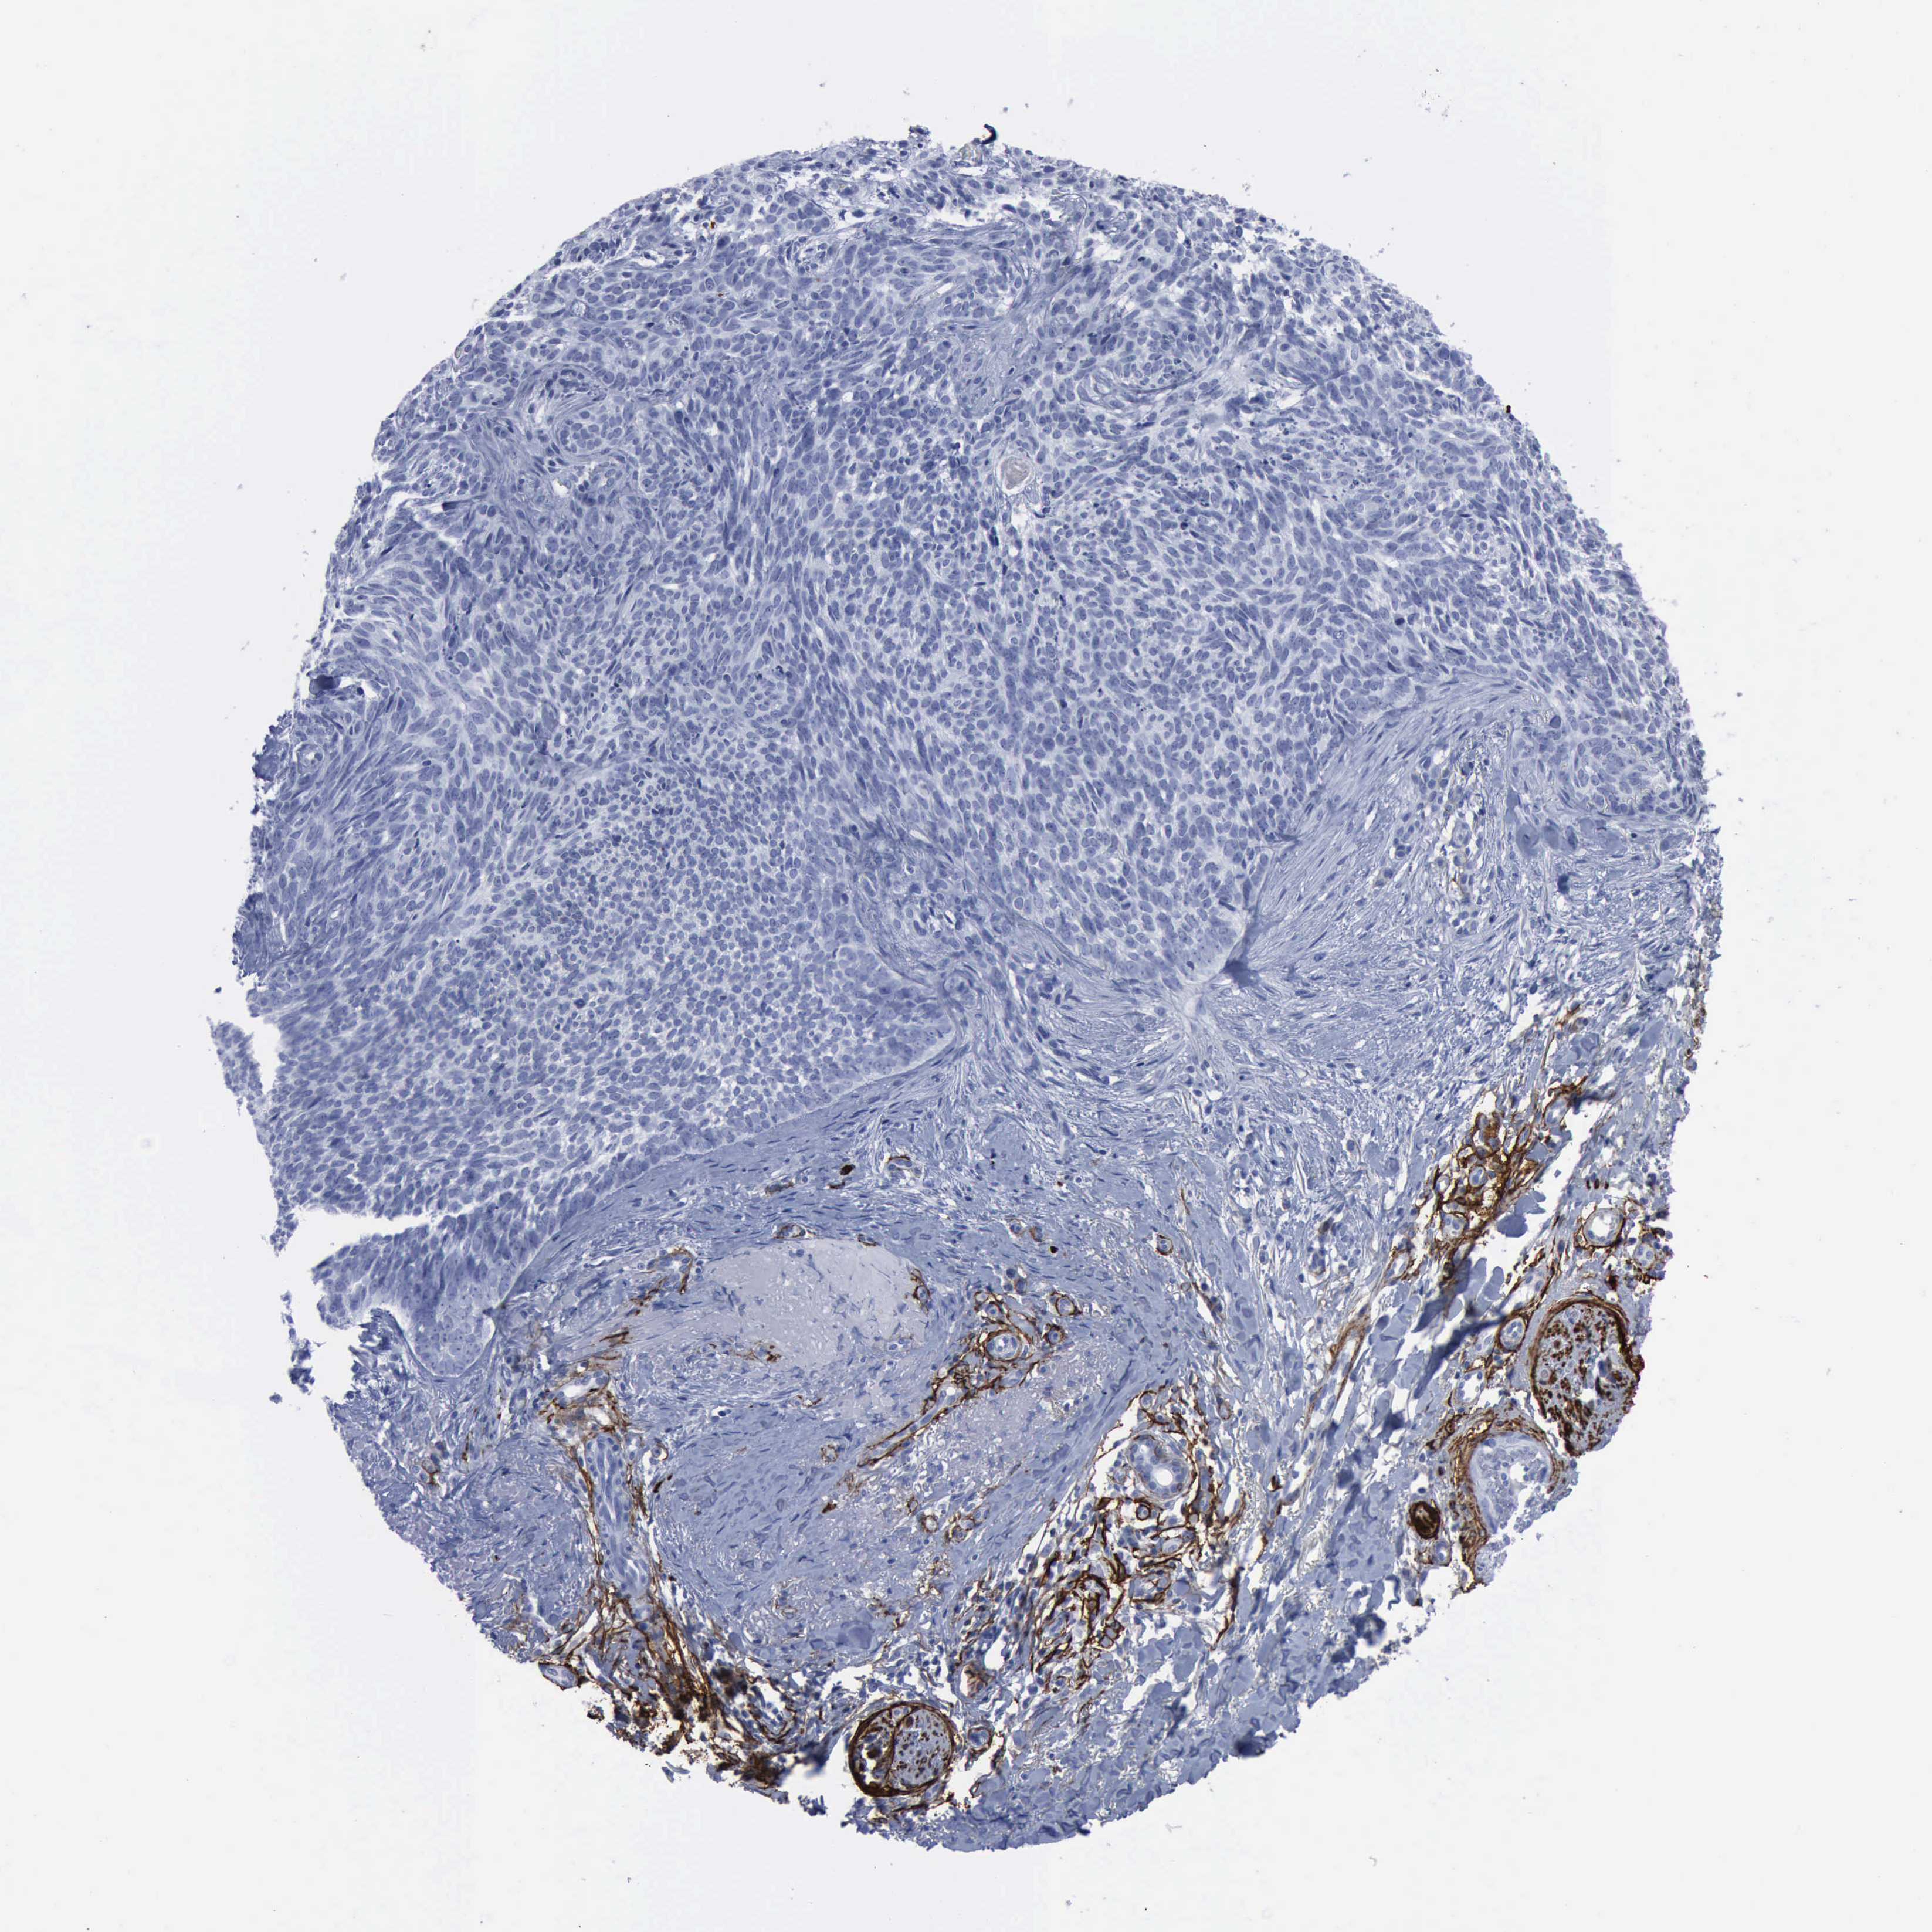

CANCER SKIN CANCER Show tissue menu

Basal cell and squamous cell cancer

SKIN CANCER - Protein expressioni

A mouse-over function shows sample information and annotation data. Click on an image to view it in a full screen mode. Samples can be filtered based on level of antibody staining by selecting one or several of the following categories: high, medium, low and not detected. The assay and annotation is described here.

Each image is clickable and will lead to virtual microscopy that enables deeper exploration of all samples and also displays staining intensity scores, fraction scores and subcellular localization as well as patient and tissue information for each sample.

Antibody HPA004765

Squamous cell carcinoma, NOS

Basal cell carcinoma